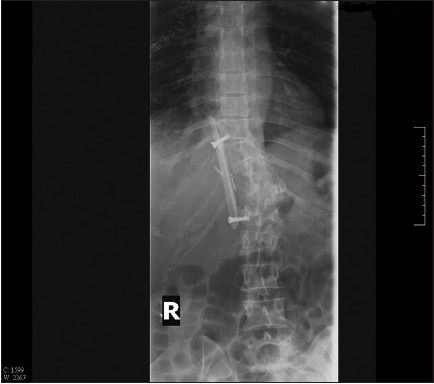

Figure 4: Postoperative thoracolumbar plain radiograph